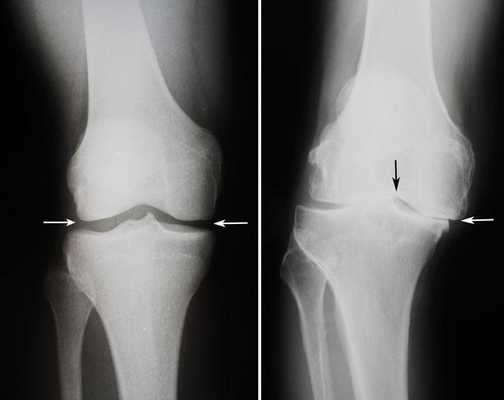

Динамика болезни на рентгене.

Откладывать хирургию при гонартрозах 3-4 степени чревато деформацией позвоночника. Это происходит из-за хромоты. Дегенеративные процессы артроза глубоко затронут кости, из-за чего они приобретут хрупкость, потеряют плотность и зафиксировать к ним компоненты импланта станет сложно.

Посмотрите на рентген, на нем вы видите, до какой степени при запущенном гонартрозе изношен гиалиновый хрящ, обеспечивающий гладкое скольжение суставных поверхностей. Концевые участки костей грубо деформируются нарушая функции сгибания и разгибания конечности вызывая интенсивный болевой синдром.